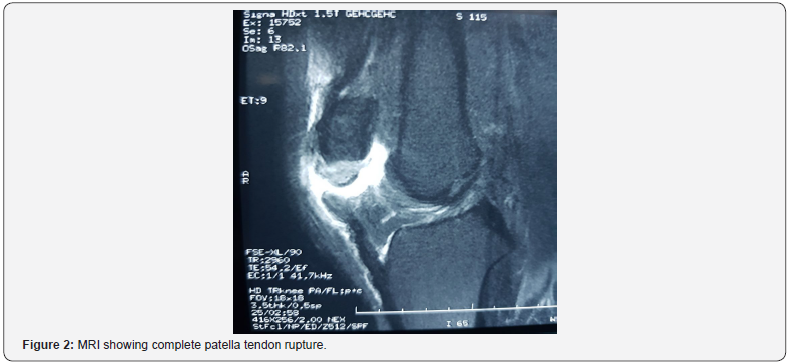

Patient, 23-year-old amateur boxer, was admitted to Accidents and Emergency department for functional impairment of the right lower limb resulting from a ski accident one (01) hour prior to his admission. Patient recounted direct right knee impact on fall with blocked foot and body projecting backwards. There was no history of chronic illness, nor previous trauma or medication. Physical examination found a conscious patient in good general condition with a body mass index of 25kg/m². Musculoskeletal examination noted a painful right knee swelling and a palpable infra patella gap (Figure 1), Patient could not maintain active right knee extension. There was no overlying wound and neurovascular exam was unremarkable. Plain knee X-ray ruled out patella fracture. MRI came back for complete rupture of the patellar tendon with a Caton-Deschamps index at 1.4 and slight knee hemarthrosis. Cruciate ligaments were intact and so were the menisci with no bony abnormalities (Figure 2).

Similar to quadriceps tendon, ultrasonography and MRI are very useful in the preoperative workup as well specifying the location of patella tendon rupture [5]. MRI remains the gold standard as it could rule out associated soft tissue damage notably anterior cruciate ligament injury or meniscal lesions that usually accompany high-energy trauma.